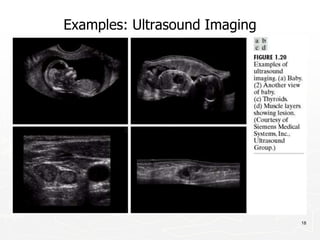

Examples: Ultrasound Imaging